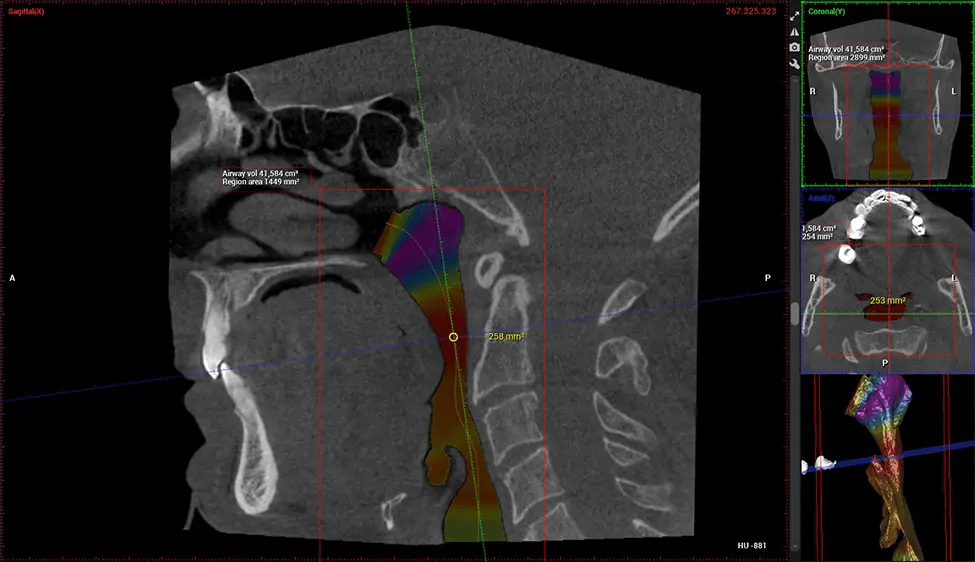

Cone Beam Computed Tomography (CBCT) is an advanced imaging technique used in dentistry and maxillofacial surgery to obtain detailed 3D images of the oral and maxillofacial structures. At Dr G Dental Studio, our CBCT scanners utilize a cone-shaped X-ray beam and a specialized detector to capture images from different angles. A computer then combines these images to create a 3D representation of the patient’s oral anatomy.

This 3D scan, called cone beam computed tomography, gives your dentist a more complete image of your oral anatomy and disease processes than a traditional X-ray. Unlike conventional X-rays, which capture a 2D image of your mouth from various angles, a 3D scan takes multiple digital X-rays for one image. It provides a complete view of your jaw, teeth, nerves, and soft tissues. This enhanced view allows dentists to detect minor issues not visible in traditional 2D scans, such as impacted wisdom teeth or bone fractures in the sinus cavity.

There are many benefits to using CBCT technology, especially compared to the traditional 2D X-ray format. One of the most significant advantages of CBCT scans is that they provide much more information than traditional X-rays. A scan lets your dentist see images from all angles of your jaw and mouth, including your sinuses, nasal cavity, cheekbones, and other surrounding areas. This added information helps your dentist craft a comprehensive treatment plan that addresses all aspects of your oral health.

Another significant benefit is that 3D imaging provides more precise images of your bone structure. These images are more detailed, providing you with a more accurate diagnosis. An accurate diagnosis means better treatment for you.

After the scanning process, the captured X-ray images are processed by the CBCT software, which applies algorithms to reconstruct a detailed 3D image of the scanned area. The software compiles these individual X-ray images and creates a digital 3D representation of the patient’s anatomy. The reconstructed 3D CBCT image can be viewed and analyzed by the dentist or radiologist. This image can be manipulated, rotated, and zoomed in or out to examine specific structures and evaluate the patient’s condition.